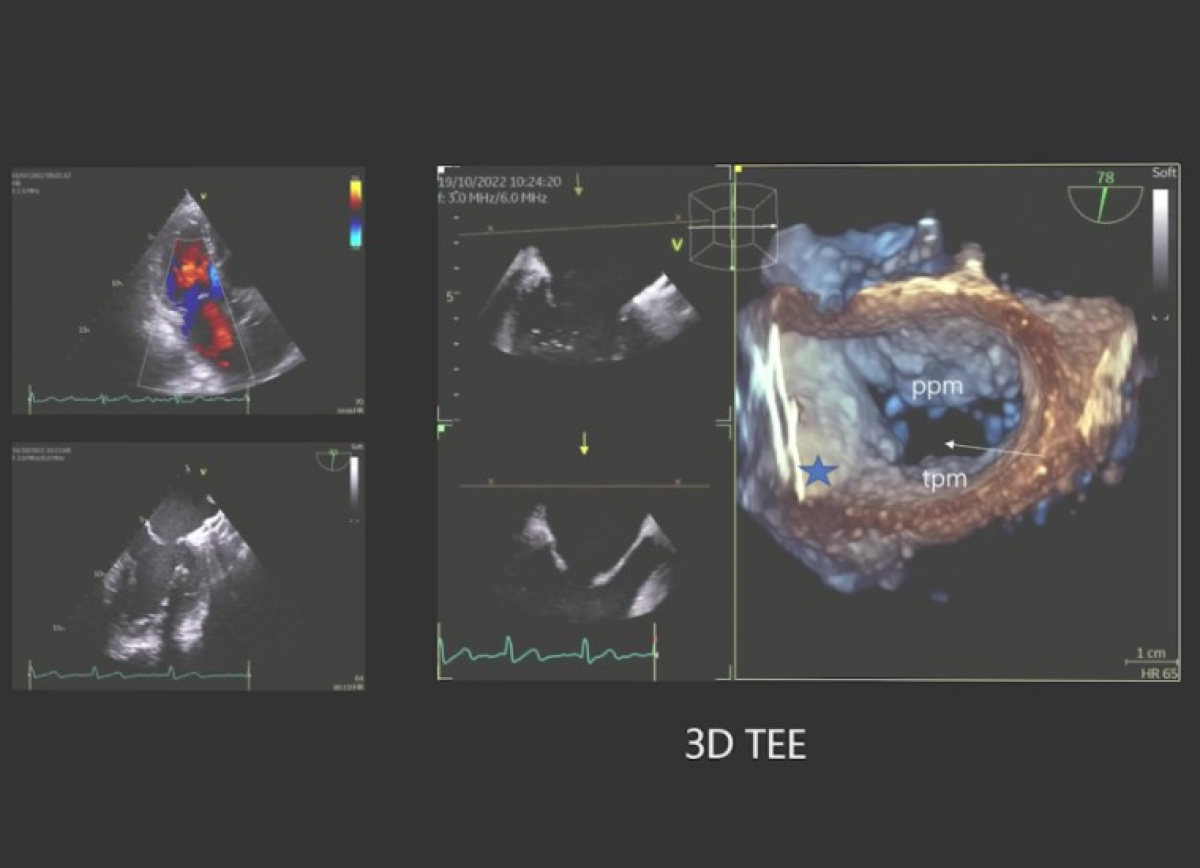

Niescalenie mięśnia lewej komory. Ubytek w przegrodzie międzykomorowej. Zwężenie podzastawkowe pnia płucnego. Ubytek w przegrodzie międzyprzedsionkowej.

Echokardiografia przezklatkowa i przezprzełykowa.

Echokardiografia trójwymiarowa.

Diagnostyka niescalenia mięśnia lewej komory.

Ocena pacjentów ze złożonymi wadami wrodzonymi serca.